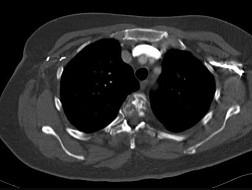

问题 女,47岁,背痛半月余,2个月前被诊断为乳腺癌肝转移,请结合影像学检查,选出最可能的诊断 ( )

选项 A、椎体压缩骨折 B、脊椎退行性变 C、脊椎转移瘤 D、化脓性脊柱炎 E、脊椎结核

答案 C